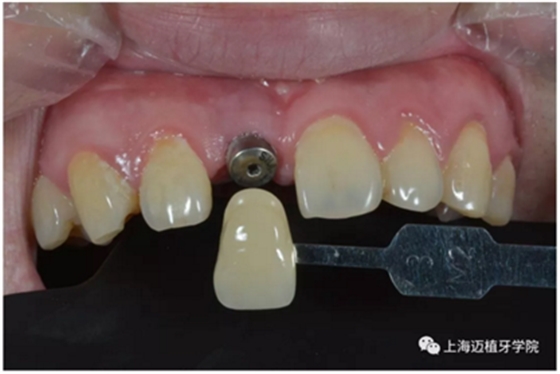

比色:3/M2

氧化鋯個性基臺

口內(nèi)個性化基臺:

戴牙 最終修復(fù)效果